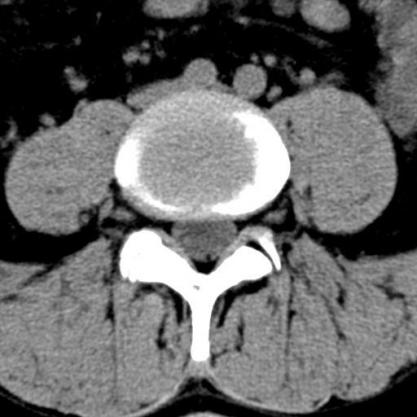

Lendenwirbelsäule

Auch hier reicht zumeist Röntgenaufnahme in Funktion sowie eine Kernspintomographie oder eine Computertomographie aus. Bei einem Wirbelgleiten oder einer Verengung auf mehreren Höhen ist eine Myelographie nach wie vor die Untersuchung, die die wertvollsten Ergebnisse im Hinblick auf eine genaue Operationsplanung liefert.